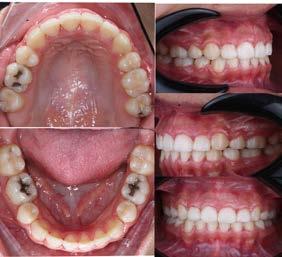

El colapso bilateral en el maxilar es una de las consecuencias más frecuentes de estos malos hábitos y por consiguiente, propicia una reducción en las dimensiones perimetrales del paladar y del arco dental, aumentando la profundización de la bóveda palatina, generando complicaciones a nivel respiratorio entre otras complicaciones, dando resultados no favorables como la respiración bucal,

acomodo no fisiológico lingual, etc.; lo cual, refleja un acompañamiento del subdesarrollo en el cuerpo y rama mandibular, el cual es un factor crítico para el acomodo de los caninos en la etapa del intercambio dental23 (Figura 40).

Acciones terapéuticas

Al haber determinado las causas que están generando el proceso de una posible inclusión canina, tomando en cuenta las consideraciones y haber obtenido un diagnóstico con la ubicación espacial del canino dentro del maxilar o mandíbula, incluyendo un posible pronóstico y sus limitantes, podemos planificar la aplicación del plan de tratamiento interceptivo, el cual se puede dividir de la siguiente manera:

Etapa ortopédica

Tiene como objetivo, la corrección de las disarmonías maxilomandibulares en su dimensión, proporción e interrelación durante la oclusión; en la que la colocación de aparatos dependerá de los planos craneofaciales a corregir (transversales o sagitales), para estimular su crecimiento o redirección de los mismos; lo que a la vez, influirá directamente a la estimulación de la osteogénesis a nivel de las suturas óseas no consolidadas y en las áreas cartilaginosas ya sea en macizos óseos de desarrollo intramembranoso o endocondral, logrando generar espacio suficiente para el trayecto y erupción canina.24

En el colapso maxilar, por ejemplo, el primer paso es corregir el plano transversal. No podremos generar el espacio necesario para el acomodo del canino y posiblemente de los dientes adyacentes en el hueso alveolar, si no existe la zona ósea basal específica que lo soporte. Los diferentes tipos de aparatos usados para este objetivo dependerán de la edad del paciente o el grado de colapso y/o profundidad de la bóveda palatina, ya que el diseño de estos estará sujeto a las condiciones anatómicas y clínicas presentes.25

Por consiguiente, la aparatología usada en la intercepción correctiva del plano transversal tiene variantes como las siguientes:

Disyuntores palatinos: tipo Hass, Hyrax, Quad Hélix, Hillgers, abanico y placa Schwarz, entre otros.26,27

Al modificar y aumentar el contorno perimetral del arco alveolar superior, se genera el espacio para permitir el acceso del canino al arco dental, además, una acción conlleva a la otra, ya que la mandíbula se estimula al mismo tiempo compensando la oclusión y estimulando el crecimiento del cuerpo, rama, orientación condílea y arco dental mandibular, generando la posibilidad de realizar movimientos de lateralidad y protrusiva en forma gnatológica y así realizar una oclusión armonizada, propiciando de esta manera la generación de espacio necesario para los caninos inferiores.28

Por otro lado, al no haber una alteración en la dimensión y plano transversal, más existe la necesidad de redirigir la dirección de crecimiento maxilomandibular, además de generar espacio para el canino, la dinámica ortopédica deberá enfocarse hacia el plano sagital.

Las diferentes aparatologías con objetivo ortopédico u ortodóntico, que en este último sería lograr distalar los dientes posteriores para recuperar u obtener espacio en el arco dental, respetando el patrón de crecimiento craneodentofacial, si está dentro de los valores estándares cefalométricos y estéticos del paciente. En caso contrario, el tratamiento ortopédico, debe considerar un enfoque doble: de intercepción con la redirección ósea bimaxilar requerida y, al mismo tiempo, obtener el espacio suficiente para el acomodo del canino. Entre las aparatologías con efecto ortopédico en el plano sagital tenemos las siguientes:

1. Arco extraoral, el cual pude ser utilizado con tracción alta, media o cervical.40,41 Péndulo o aparato de Hillgers modificado (Figura 41).

2. Mascara facial (Figura 42).

3. Bionator simple o combinado con lip bumper, entre otros (Figura 43).

Etapa quirúrgica

Algunos autores como Jacoby (1983), menciona la importancia de generar espacio suficiente para el libre acceso del canino, cuando la corona está

Figura 41.

Figura 42.

Diagnóstico y tratamiento ortodóntico interceptivo como prevención en la inclusión del canino

posicionada en dirección vestibular, ya que solamente el 17% de caninos impactados vestibularmente tienen un espacio suficiente, a comparación de los impactados donde la corona tomó la dirección hacia el paladar, ya que por lo regular en estos casos, el canino deciduo siguió estando presente sin reabsorción alguna, el cual desempeña un papel importante como mantenedor de espacio biológico; sin embargo, genera la necesidad de que el canino busque una salida emergente, que en estos casos es hacia la bóveda palatina44 (Figura 44).